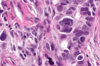

This pic tells you where the stroma is.

This is a high grade serous carcinoma.